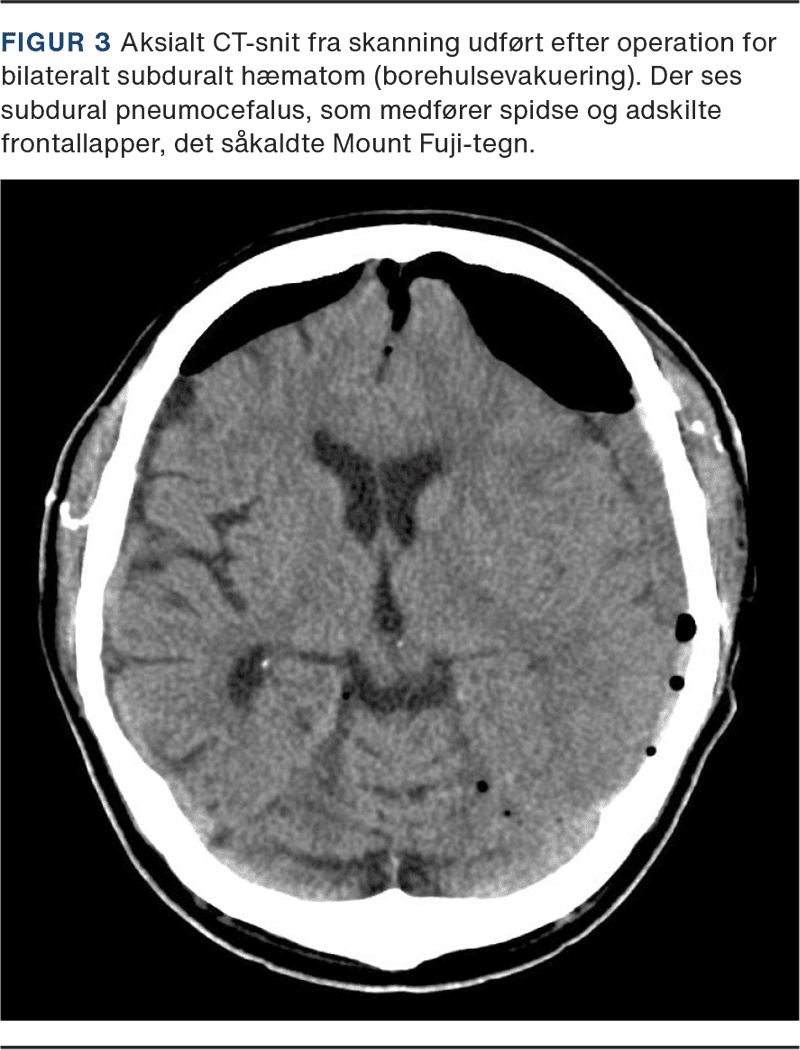

Neurokirurgiske indgreb anses for at være en af de hyppigste årsager til pneumocefalus [11, 12]. Dette er en naturlig følge af, at der ved disse operationer er behov for åbning af dura for at kunne behandle en underliggende patologi i hjerne eller rygmarv, hvilket medfører en eksponering for atmosfærisk luft. Subdural lokalisation af luften er den hyppigste (Figur 1), men afhængigt af indgrebet kan luft forekomme i alle intrakranielle kompartmenter [13, 14].